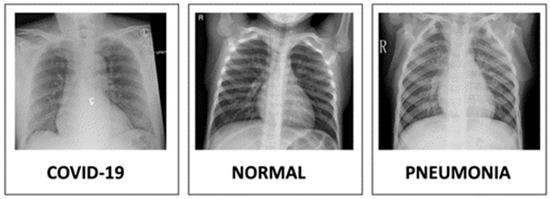

- Chowdhury, M.E.; Rahman, T.; Khandakar, A.; Mazhar, R.; Kadir, M.A.; Mah-bub, Z.B.; Islam, K.R.; Khan, M.S.; Iqbal, A.; Al-Emadi, N.; et al. Can AI help in screening viral and COVID-19 pneumonia? arXiv 2020, arXiv:2003.13145. [Google Scholar] [CrossRef]